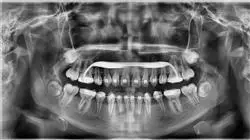

L'ortodonzia è stata la prima specialità all'interno dell'odontoiatria e seconda solo all'oftalmologia nell'ambito delle scienze della salute. In questo senso, per specialità si intende la presenza di un'organizzazione professionale, di una letteratura e di una relativa istruzione di tipo specifico. Le sue peculiarità in termini di diagnosi, tipo di trattamento, obiettivi e basi scientifiche richiedono una prassi professionale specifica.

Insieme alla terapia ortodontica, vengono applicati trattamenti ortopedici dento-facciali per ottimizzare i risultati e spesso agevolare la riabilitazione delle strutture e il miglioramento della funzione.

L'ortopedia dentofacciale è una disciplina dell'odontoiatria che si occupa della diagnosi, della prevenzione e del trattamento delle malocclusioni e delle deformità della mascella e dei denti. Questo settore sta diventando sempre più importante e richiesto al giorno d'oggi, grazie alla crescente consapevolezza dell'importanza della salute dentale e dell'estetica del viso. In TECH offriamo un Esperto Universitario in Ortopedia Dentofacciale pensato per soddisfare le esigenze dei professionisti che desiderano ampliare le proprie conoscenze e competenze in questo settore. Il nostro programma è interamente online, il che significa che gli studenti possono partecipare alle lezioni da qualsiasi luogo. Questo garantisce una grande flessibilità e comodità, in quanto i partecipanti possono adattare il loro programma di studio alle loro esigenze personali e lavorative. Inoltre, le lezioni online consentono agli studenti di interagire efficacemente con i professori e i compagni di corso, grazie a strumenti di comunicazione avanzati e piattaforme di apprendimento online.

Specializzati in ortopedia dentofacciale con TECH